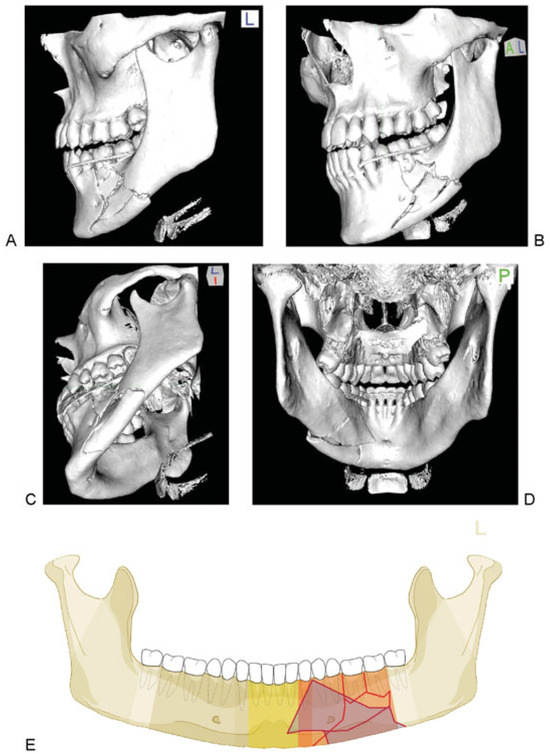

Figure 7.

Symphysis fracture of grade 0 fragmentation. (A–E) Imaging: CT scans, 3D reformatted overview, axial slice to identify tooth roots, 3D reformations in detail: Anterior view, basal view, lingual view. Narrative description: Oblique parasymphyseal fracture on the outer surface beginning in the midline interdentally between middle incisors runs downwards to the left and ends at the inferior mandibular border without crossing the anterior transition zone. On the basal and lingual side jagged fracture course indicating a fracture in the frontal plane. (F) Code Level 3: 91 S0. This case example CMTR-91-001 is made available electronically for viewing using the AOCOIAC software at www.aocmf.org/classification.